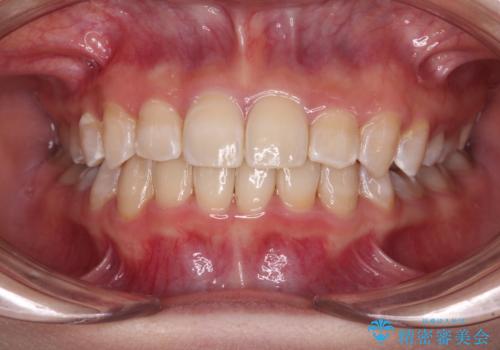

上下の骨幅を改善したことで、スムーズに歯列矯正を行うことができました。

矯正治療中に近医で銀歯を外す治療を開始したため、治療後に奥歯の咬み合わせが不十分ですが(こちらは近医での治療により改善するとのこと)、歯列と咬み合わせが改善され、患者様には大変満足していただきました。